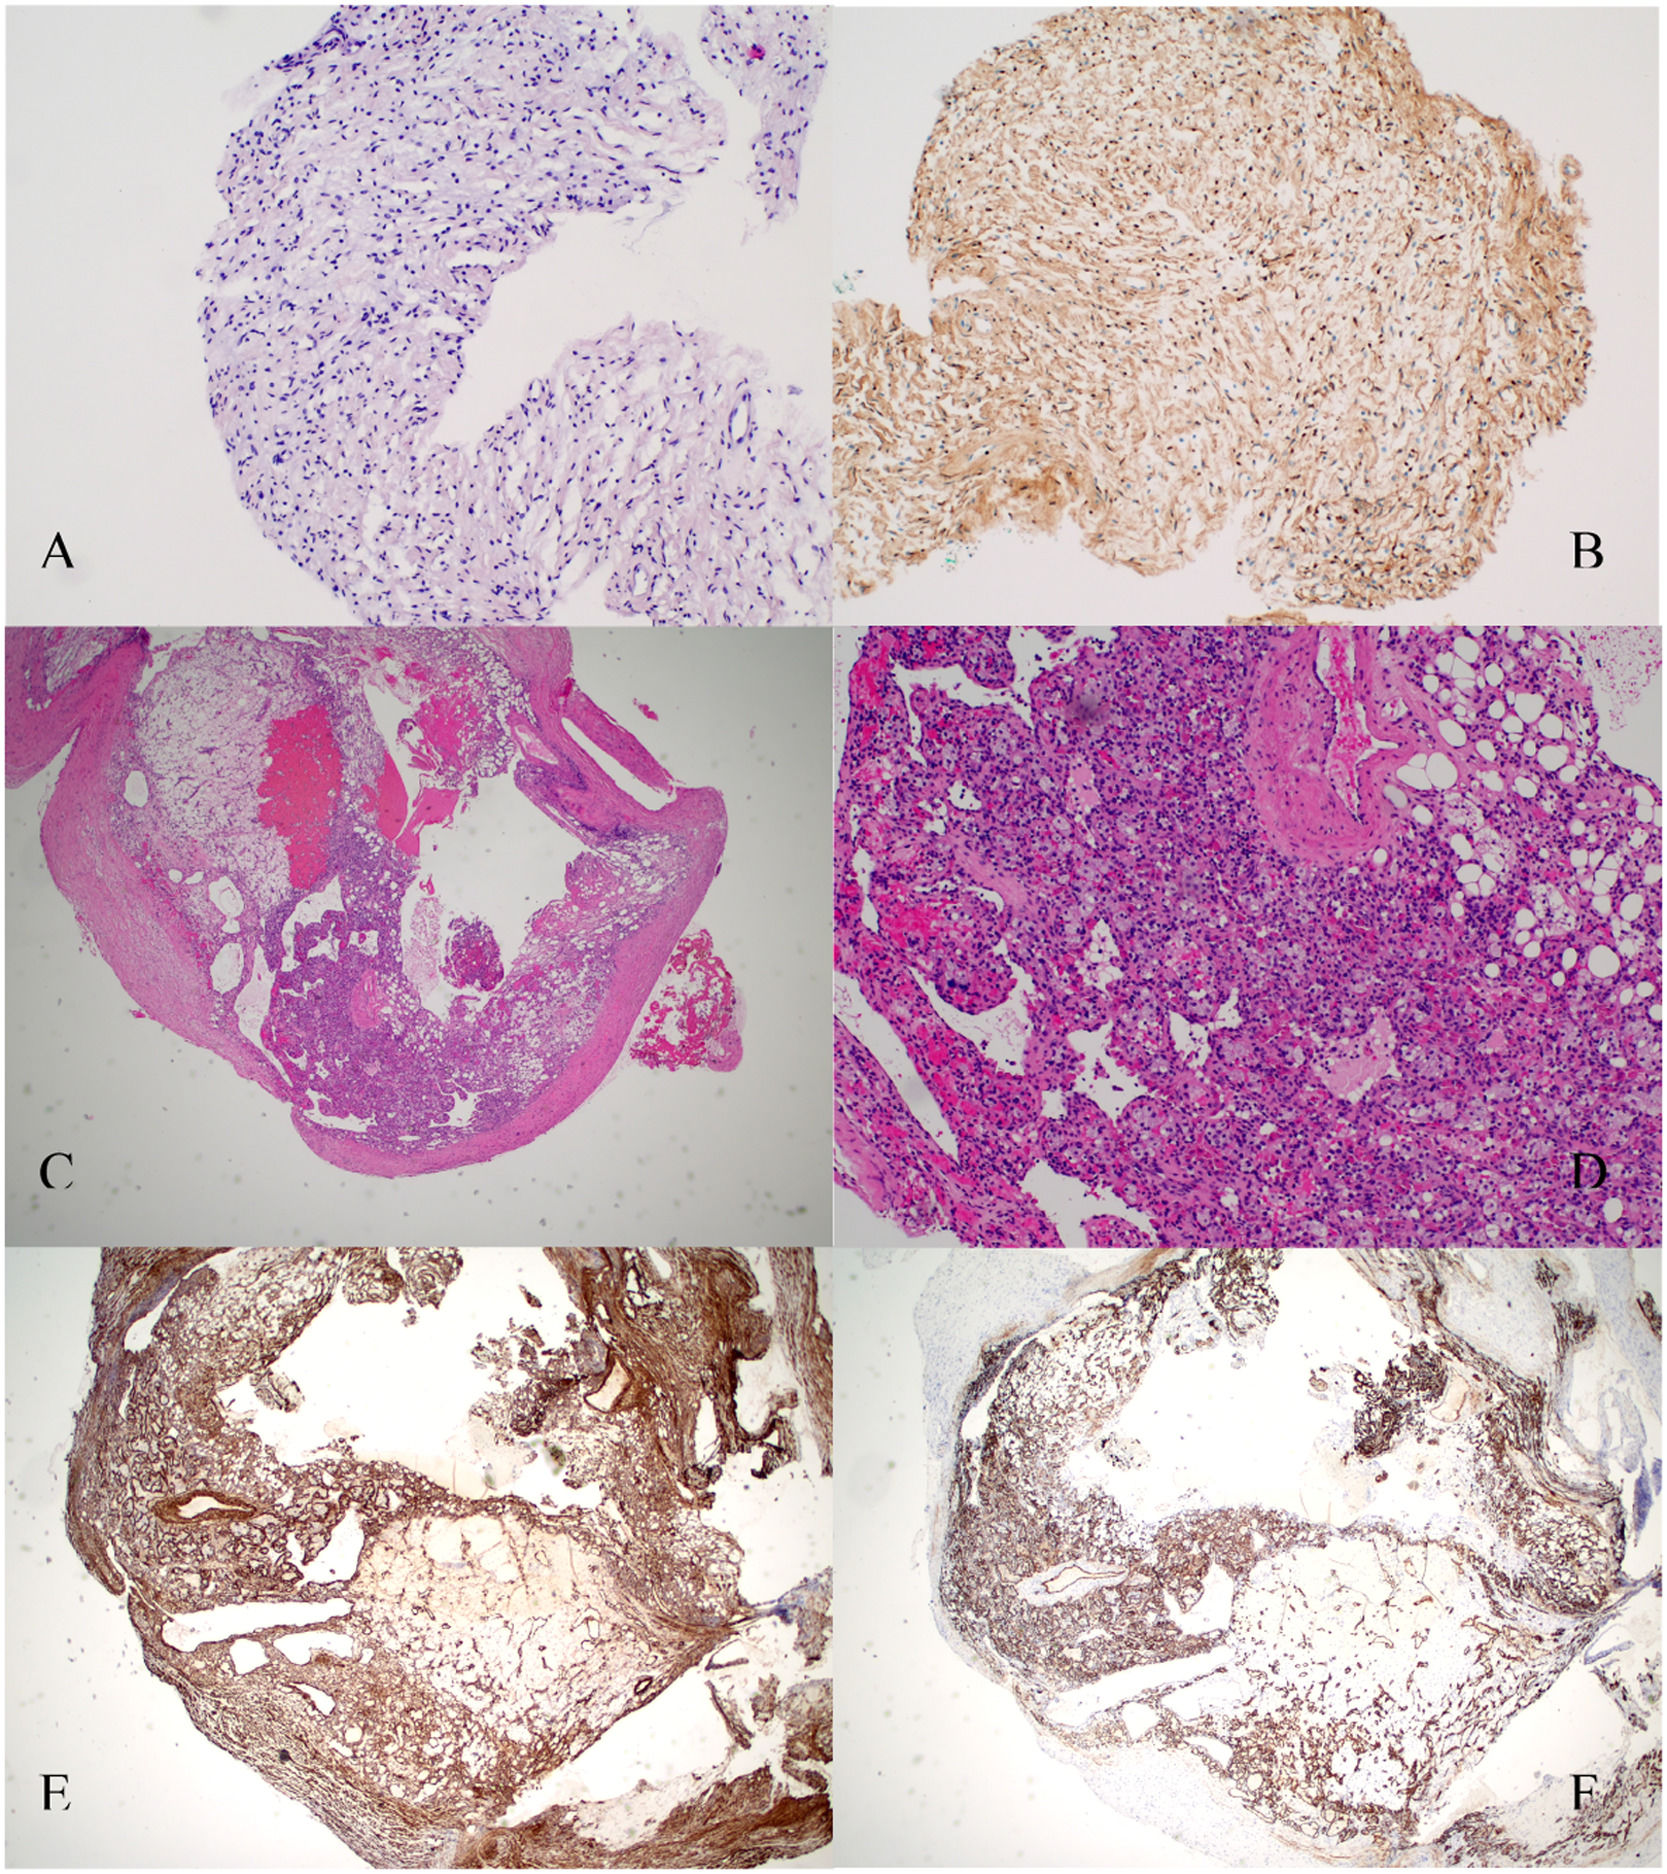

To confirm the cause of the mediastinal lesion, the patient underwent medical thoracoscopy. A hypervascular, sessile mass was observed in the prevascular mediastinum and subsequently biopsied (Fig. 2). The tumour was not separated from the aorta during the procedure. Histological examination of pleural fragments showed vascular congestion, alveoli filled with macrophages, and compression of the alveoli by a fibroadipose tissue 'mass' (MDM2-) and smooth muscle (actin+), accompanied by capillary proliferation (CD34+). Thrombi were frequently present. No necrosis or mitoses were detected. Histochemical investigation for microorganisms, including PAS, Ziehl-Neelsen, and Grocott staining, yielded negative results. Immunohistochemical analysis was performed to explore other neoplasms, and results for calretinin, BER-EP4, S100, CD1a, Melan-A, HMB45, and p53 were negative (Fig. 3)

Histopathology sections. A. Lesion in the pectoralis major muscle sheath. Hematoxylin and eosin staining. B. Lesion in the pectoralis major muscle sheath. Schwann cells are strongly positive for S-100 protein (×10). C. Hematoxylin and eosin staining revealing features of the excised pleural mass with mature adipose tissue, thick-walled blood vessels and smooth muscle cells. Pathological findings of angiomyolipoma. D. 10× magnification. E. Pleural lesion. Smooth muscle actin immunohistochemical showed diffuse positivity smooth muscle cells (×10). F. Pleural lesion. Immunostaining for CD34 antigen revealed many CD34-reactive capillaries combined with mature adipocytes (×10).

Angiomyolipomas are characterised by the expression of melanoma markers (HMB45 and melan-A) in tumour cells, as well as smooth muscle component positivity for muscle actin-specific marker (HHF35) and desmin.2,8 Although the immunohistochemical study did not fully support the diagnosis, the observed morphological features strongly suggest that angiomyolipoma is likely the correct diagnosis, considering its rarity in the mediastinum and the limited number of reported cases in the literature. The histology was reviewed by three different pathologists.